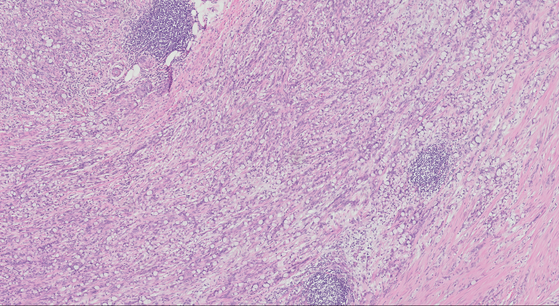

solitary rectal ulcer syndrome/mucosal prolapse.

Fibromuscular hyperplasia/obliteration of lamina propria

Architectural distortion of colonic mucosa/epithelium

Hyperplastic/villiform, regenerative surface with mucin loss

Inflammation, erosion, ulceration, pseudomembranes

Capillary proliferation with dilation below surface

Dense submucosal fibrosis with cysts often present

features of solitary rectal ulcer syndrome

A

Superficial mucosal ulceration and villiform change

Crypt hyperplasia and elongation with focal dilation (some glands diamond shaped)

Fibromuscular hyperplasia of lamina propria

Thickened muscularis mucosae with splayed fibers

Ectatic capillaries

Minimal inflammation

May have inflammatory pseudomembranes

Late changes resemble colitis cystica profunda

Image: showing muscularis mucosae thickening and fibromuscular hyperplasia of the lamina propria